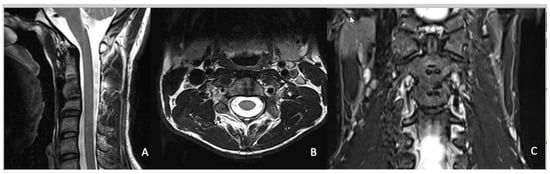

3.2. Radiological Outcomes